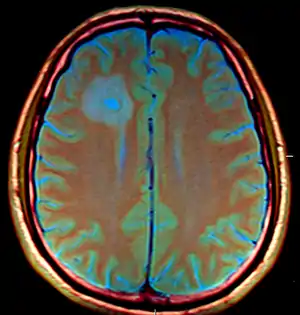

| Amoebic brain abscess caused by Entamoeba histolytica | |

The CT images for the abscesses caused by Entamoeba histolytica are completely indistinguishable from the abscesses caused by any other organisms or causative agents. However, the brain abscesses are often observed in the frontal lobe or the basal ganglial regions.[3]